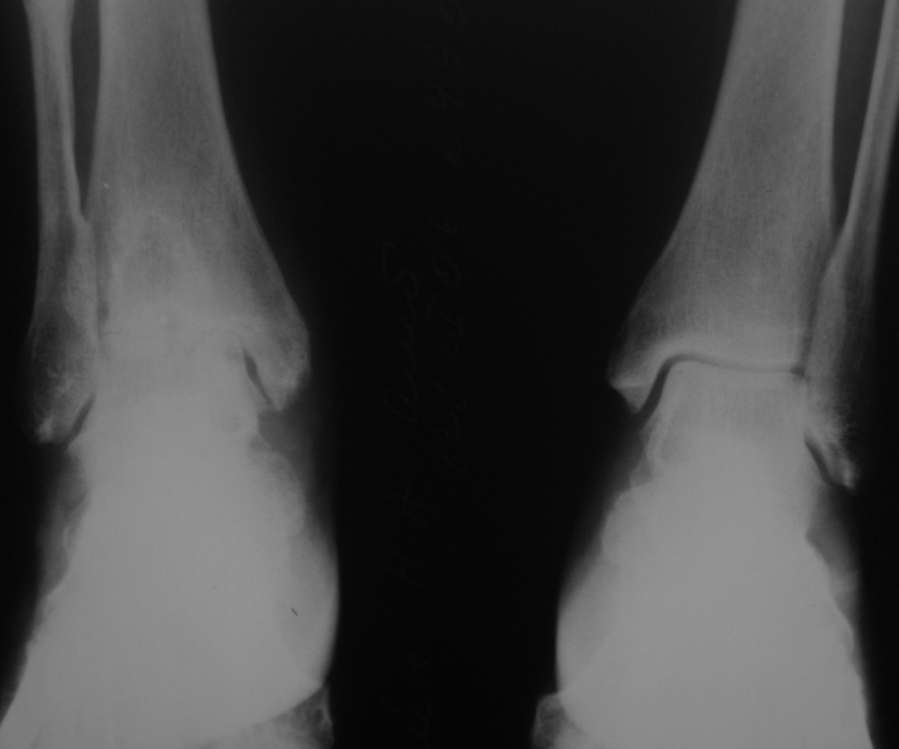

Уважаемые коллеги, разъясните ситуацию.Пациентка, 45лет. 9 месяцев назад произведен синтездвухлодыжечного перелома правой голени.

Конструкции на данный момент удалены. Объем движений на фото. Сейчас беспокоят скованость в области сустава, боли к концу рабочего дня - классическая клиника артроза.Пропила 4 курса найз. Откуда артроз такой выраженности (на рентгенограмме)? Поможет ли консервативное лечение и какое поможет наверняка?

Артроз, во-первых, вследствие неконгруентности суставных поверхностей - имеется укорочение малоберцовой кости; во-вторых имеется синостозирование берцовых костей (вместо тугоэластисчного синдесмоза).

Но укорочение - 3мм, и потом суставная поверхность наружной лодыжки не несет осевой нагрузки

Считаете ли Вы, что объем движений близкий здоровому суставу обеспечивается только подтаранным суставом?

> Считаете ли Вы, что объем движений близкий здоровому суставу обеспечивается только подтаранным суставом?

Нет, подтаранный сустав в основном обеспечивает движения стопы во фронтальной плоскости. Ограничение движений в г\ст суставе компенсируется движениями в среднем отделе стопы